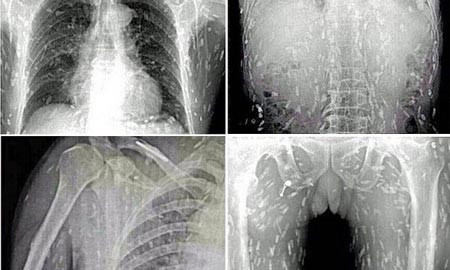

Người đàn ông không được tiết lộ danh tính ở Trung Quốc đã tới thăm khám bác sĩ với các triệu chứng đau dạ dày và ngứa ngáy da. Anh kinh hoàng khi được thông báo, kết quả chiếu chụp hé lộ toàn bộ cơ thể anh đã bị nhiễm sán dây dày đặc sau khi ăn quá nhiều sashimi - gỏi cá hoặc thịt kiểu Nhật.

Các bác sĩ tin rằng, một số thịt hoặc cá sống trong món gỏi sashimi chắc chắn đã bị nhiễm khuẩn. Người đàn ông đã được chữa trị tại Bệnh viện Nhân dân Quảng Châu số 8 tại tỉnh Quảng Đông, miền đông Trung Quốc.